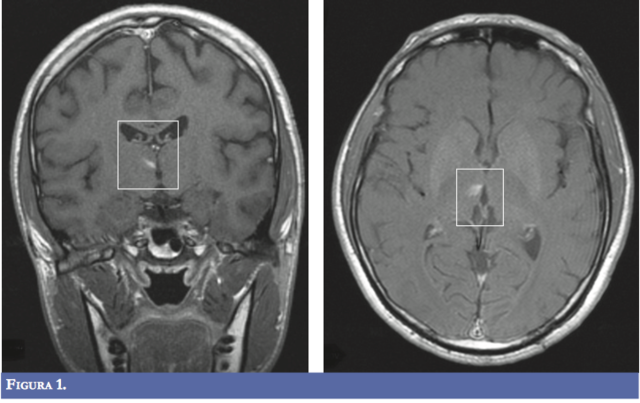

• Resonancia magnética encefálica.

Resonancia magnética encefálica.

Se evidenció lesión que restringía la difusión, visible en FLAIR y T2.